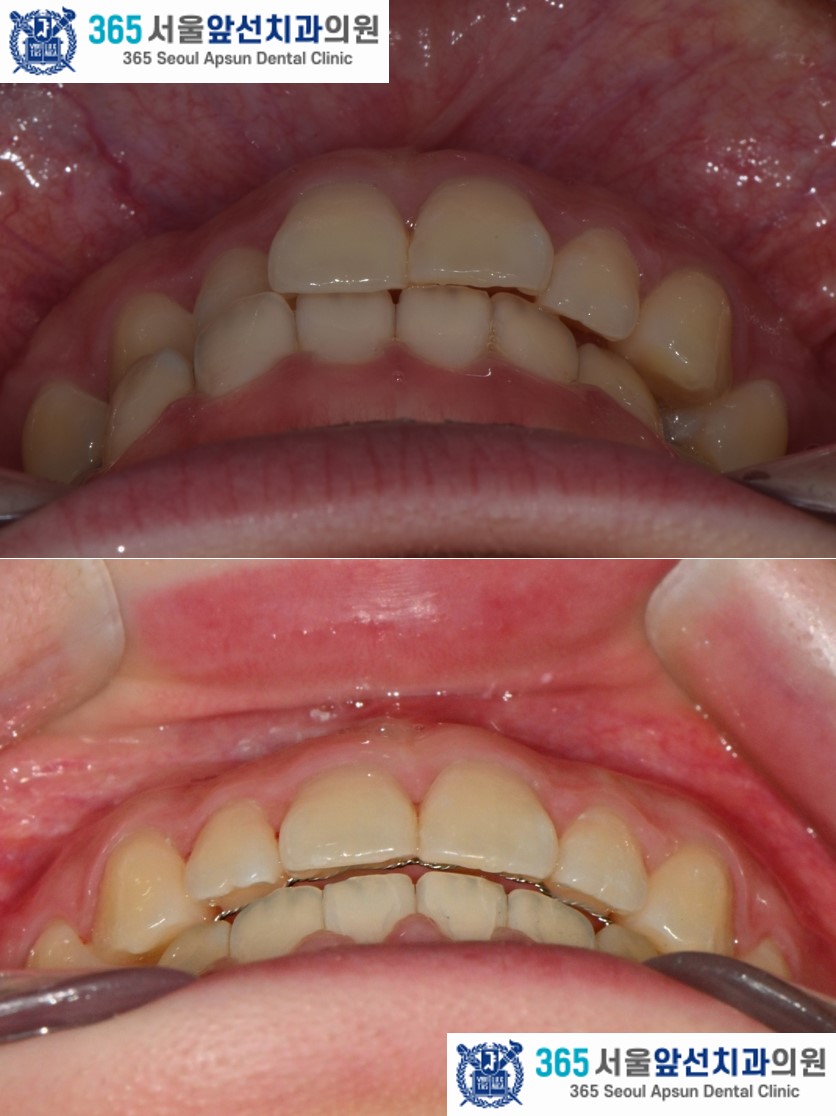

촬영일시 : 2024.10.23. / 2025.11.12. 반대로 물리는 이 때문에 입술이 비틀어져 보인다는 고민으로 내원하신, 성장이 완료된 10대 청소년 환자 분의 증례를 소개드리겠습니다.

촬영일시 : 2024.10.23. 치료 전, 우측 측절치와 견치(송곳니)의 반대교합과 정중선 불일치가 관찰됩니다. 양측 상악 측절치가 5.6mm 폭경으로 왜소치 경향을 보이며 Bolton 의 전치부 비율이 86.73으로, 이상적인 윗니와 아랫니 앞니의 비율을 고려한 폭경에 비해 5.0mm가 부족합니다. 이 경우, 왜소치의 폭경을 키워 수복한다면 이상적인 교합을 형성할 수 있습니다. 해당 환자분께서는 왜소치의 수복 없이 치료하기를 원하셔서, 보상적으로 하악 치열의 폭경 감소와 Canine key compromise를 통해 최대한 심미적이고 기능적인 교합을 만들어드렸습니다.

촬영일시 : 2025.11.12. 치료 후의 모습입니다. 2024년 11월 16일 치료를 개시하여 2025년 11월 12일에 교정치료를 종료하였으며 총 12개월의 치료기간이 소요되었습니다. 치열이 가지런하게 배열되었고 목표하였던 반대교합의 해소, 정중선 불일치 개선이 완료되었습니다. 왜소치 수복 없이 구치부 1급 관계와 견치 유도 및 전치 유도가 가능한 교합이 잘 만들어졌습니다. 더불어 입술의 비틀어짐도 자연스럽게 해소되셨습니다. ![]() 촬영일시 : 2024.10.23. / 2025.11.12. 앞니의 반대교합이 있으셨던 환자분의 12개월 간의 치료 증례를 소개해드렸습니다. 환자분께서 정기적인 내원에 적극 협조해주셔서 치료기간이 단축되었던 것 같습니다.^^ 반대교합, 정중선 불일치, 비뚤한 치열이 고민이신 환자분들께서는 내원하셔서 교정 진단 받아보시길 바랍니다. 감사합니다.